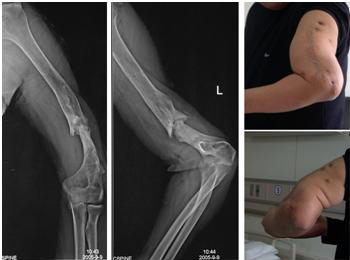

图1:肱骨干骨折11年不愈合,外院4次手术,患者左上臂存在异常活动。

FIGURE 1: After 11 years and four operations in other hospital, nonunion and

abnormal movement existed in left upper arm.

11年“断臂”终能伸屈

www.thebeijingnews.com · 2006-2-4 1:45:55 · 来源: 新京报

术前已出现严重骨缺损和骨萎缩,不日可恢复正常功能

本报讯(记者魏铭言通讯员姚永玲牛小燕)昨天,“断臂”11年的贾先生,在北医三

院骨科医生的指导下,终于可以重新自由伸屈自己的左臂了。

贾先生回忆,1994年10月,他在出差途中遭遇车祸,左胳膊开放性骨折,肱骨干完全

断开。医生为他实施了切开复位内固定手术。但时隔半年,他的左胳膊仍肿胀、疼痛得不

能活动。到医院检查发现,伤臂的桡神经损伤严重。此后,他接受了桡神经松解术等多次

手术,不但没有痊愈,左臂还出现了肢体内翻畸形。此后,经过多次手术仍不能治愈,医

生只能暂时拆除伤臂的外固定架,让左臂几乎成了“断臂”。

去年年末,贾先生拖着“断臂”来到北医三院骨科求治。医生检查发现,贾先生的伤

臂经多次手术,骨折处已出现严重的骨缺损和骨萎缩,必须重新植入新骨并牢固固定。院

方由4位医师共同为贾先生实施手术,首先彻底清除了“断臂”内的瘢痕及硬化骨质;然后,

对断臂处进行植骨;最后,精细的螺丝钉将新骨与旧骨密切、牢固地结合起来。

手术后两天,贾先生的左臂能抬起了。经过一个月的锻炼,终于可以自由伸屈。医生说,

再经过一段时间的功能训练,贾先生的左臂就可以拎东西,正常工作了。